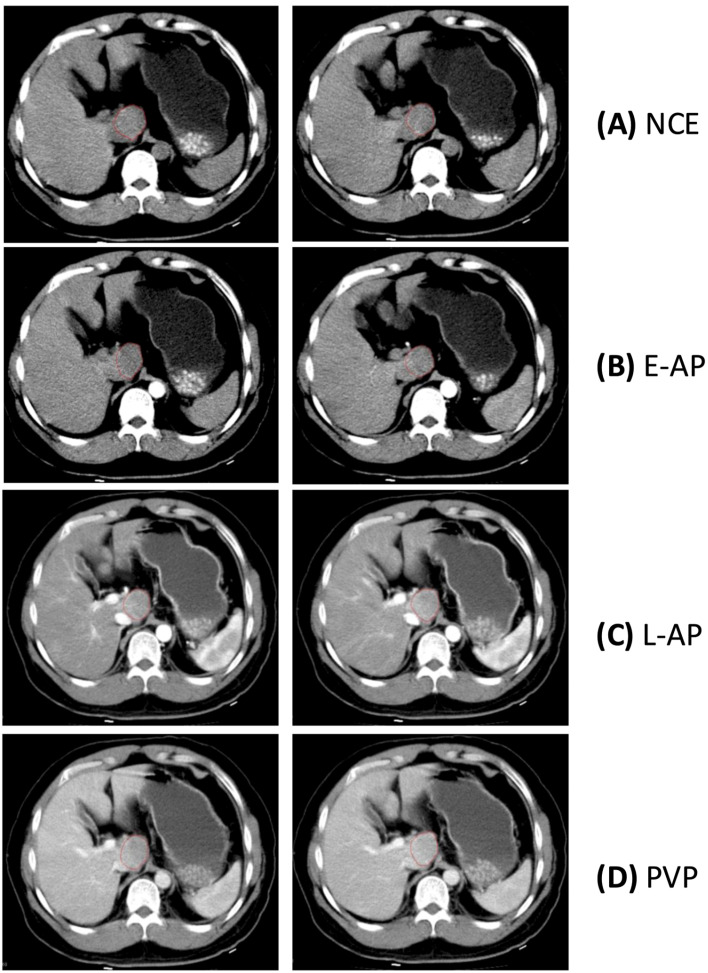

Methods: In this study, we investigated the variability of maximal lesion diameter and mean lesion density of HCC lesions on CT scans across four different contrast enhancement phases: non-contrast-enhanced phase (NCE), early arterial phase (E-AP), late arterial phase (L-AP), and portal venous phase (PVP). HCC lesions were independently segmented by two expert radiologists. For each pair of a lesion's scan timepoints, one was selected randomly as the baseline measurement and the other as the repeat measurement. Both absolute and relative differences in measurements were calculated, as were the coefficients of variance (CVs). Analysis was further stratified by both contrast enhancement phase and lesion diameter.

Results: Lesion diameter was found to have a CV of 5.11% (95% CI: 4.20-6.01%). About a fifth of the measurement's relative changes were greater than 10%. Although there was no significant difference in diameter measurements across different phases, there was a significant negative correlation (R = -0.303, p-value = 0.030) between lesion diameter and percent difference in diameter measurement. Lesion density measurements varied significantly across all phases, with the greatest relative difference of 47% in the late arterial phase and a CV of 22.84% (21.48-24.20%). The overall CV for lesion density measurements was 26.19% (24.66-27.72%).